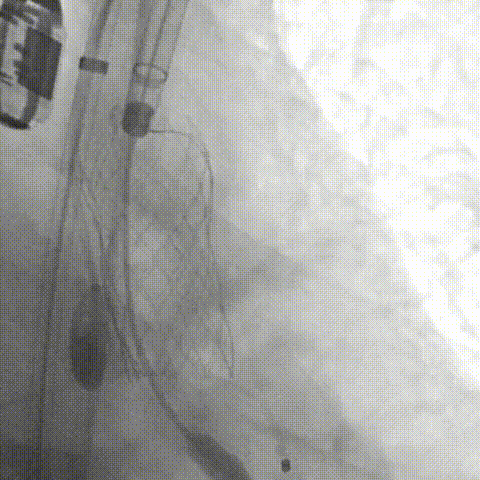

周达新教授 复旦大学附属中山医院 共识引路,干瓣启新,共赴临床解决方案:当前,结构性心脏病的介入治疗已迈入微创化、精准化的新时代。技术的革新、创新器械的上市,都是我们中国技术领跑的印证,《专家共识》的应运而生是中国医生对于行业“规范化”的践行,让治疗更精准、让医者更贴近“以患者为中心”的医疗本质。 潘文志教授 复旦大学附属中山医院 严谨求真重思考 创新临床互验证:在医学的漫长征途中,新器械的突破与严谨的临床研究是两大核心驱动力。拥抱创新的同时需要严谨求证,预装干瓣作为创新器械,其即取即用的特性可以很好的适配“急诊”的场景,此外,国产创新不是简单的复制,干瓣的瓣叶质地不是字面意思“干”的,而具“曲柔性”。所以,需要多看多测,才能全面了解一款产品。《经导管心脏瓣膜治疗术》的问世也是凝结着我们带着临床思维思考的结晶的“独家秘笈”,希望能够将“来时的路”变成未来行业同行者的“高效学习之路”! 患者病史 多病共存陷困境,主动脉瓣狭窄成 “首要威胁” 现病史:患者反复活动后胸闷2年余,无胸痛、心悸,无头晕、晕厥等不适,未予重视。患者轻微体力活动(快走、爬楼梯)即胸闷气促,静息及夜间无不适,无咳嗽、心悸等症状。为进一步诊疗收入我科,患病以来精神、食欲、睡眠、二便及体重均正常。 既往史: 2025年5月7日因小便不畅至外院住院病理穿刺确诊前列腺癌,期间检查心超提示主动脉瓣钙化伴重度狭窄,遂暂缓前列腺手术。2025年05月30日至我院就诊。 2025年5月20日开始服用比卡鲁胺片。患者血脂异常,长期服用丹参滴丸,麝香保心丸,心通颗拉。 手术史外伤史:10年前行肺手术,具体不详。否认外伤史。 入院检查 心电图提示:窦性心动过缓;ST-T改变; 心超显示:主动脉瓣钙化伴重度狭窄及轻度反流,Vmax 4.8m/s、PGmax 93mmHg、PGmean 47mmHg;左房增大,左室壁增厚。 冠状动脉CT造影:左前降支中段浅表心肌桥,主动脉瓣增厚伴重度钙化,主动脉粥样硬化。 术前CT 三叶瓣,中度钙化,主动脉根部直径25.4mm,LVOT直径23.5mm 双侧冠脉开口高度尚可,瓦氏窦尚可,ST尚可,升主尚可,冠脉风险小;中度钙化,心脏角度39.2°;心腔内径可,左室壁增厚。 外周走行尚可,全主动脉存在散在钙化,右侧穿刺点需避开钙化,血管内径可,血管内壁存在纤维增厚。 手术策略:右侧股动脉为主入路,使用20F大鞘;20球囊预扩,植入AV29瓣膜; 手术过程 主动脉根部造影 输送系统柔顺过弓 定位 缓慢释放瓣膜 造影观察 稳定脱钩 最终造影性钙位置良好,轻微瓣周漏 术后超声:轻度瓣周漏,术后平均压差11mmHg 出院前超声:平均压差11mmHg 在多基础疾病患者日益增多的当下,该病例也为临床提供重要启示:针对合并肿瘤、既往手术史的复杂瓣膜病患者,需通过多学科协作(心内科、肿瘤科、麻醉科等)全面评估病情,结合精准影像技术与适配器械,制定个体化手术方案,才能在保障安全的同时,实现最优疗效。 作为中国结构性心脏病领域的标杆学术活动,中国结构周 2025为这类高水平临床病例提供了交流平台,助力推动我国结构性心脏病诊疗技术持续创新,让更多复杂瓣膜病患者受益于精准医疗方案。 ProStyle A®预装干瓣——助力临床最优化解决方案: 轻松过弓,精准可控:该病例全主动脉存在散在钙化,右侧穿刺点需避开钙化,ProStyle A®较细的尺寸+柔顺的输送系统通过性能得到了很好的验证; 平稳释放:平衡的径向支撑力降低了释放过程中的张力,流入端小锥角设计能够迅速锚定贴边; 预装干瓣 便捷顺安:金仕生物专利抗钙化技术运用纳米技术去除组织内的细胞碎片和磷脂,封闭游离醛基,从根本上阻断了瓣膜钙化的多项因素,显著提升了瓣膜的耐久性;同时,相比较传统戊二醛保存方式,干式存储最大限度的保留心包的亲水亲油平衡,还原组织天然曲柔性,进一步保障了瓣叶开合,保证长期耐久性; 专家简介 葛均波 复旦大学附属中山医院(点击查看专家详细简历) 周达新 复旦大学附属中山医院(点击查看专家详细简历) 潘文志 复旦大学附属中山医院(点击查看专家详细简历) · END ·